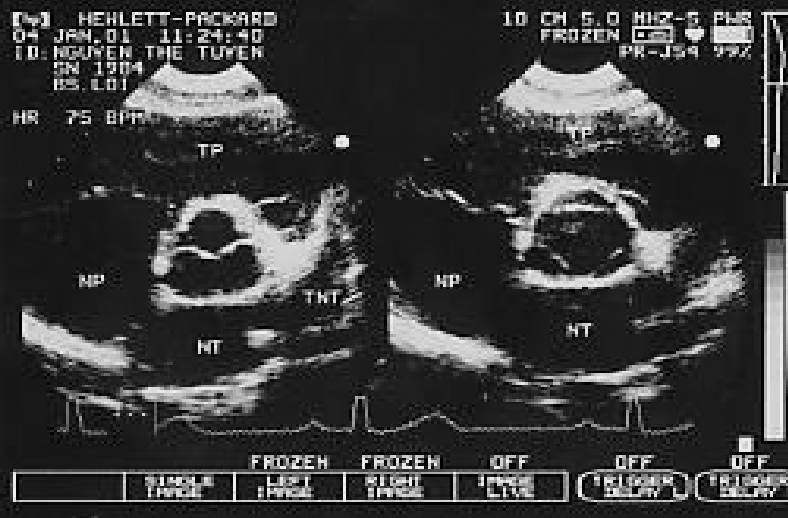

Hình 1. Hình ảnh siêu âm TM cắt ngang thất trái

- Cắt ngang thất trái ngay sát bờ tự do của van hai lá, từ trước ra sau để thấy các cấu trúc: thành ngực phía trước, thành trước của thất phải, buồng thất phải, vách liên thất, buồng thất trái, thành sau thất trái, thượng tâm mạc dính vào ngoại tâm mạc cho hình ảnh siêu âm đậm.

- Các thông số cần đo trên mặt cắt này:

+ Vào cuối thời kỳ tâm trương (khởi đầu sóng Q của phức bộ QRS trên ĐTĐ):

- Đường kính thất phải

- Bề dày vách liên thất

- Đường kính thất trái

- Bề dày thành sau thất trái.

+ Vào cuối thời kỳ tâm thu (đo ở vị trí vách liên thất đạt được độ dày tối đa):

- Bề dày vách liên thất và thành sau thất trái.